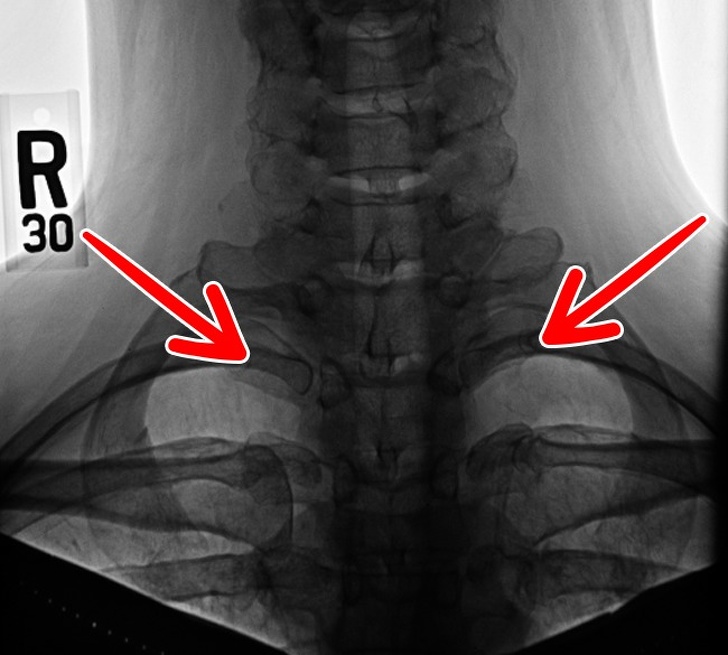

4. Шейные ребра

Набором добавочных шейных ребер, которые мы, возможно, унаследовали от рептилий, обладает менее 1 % населения Земли. У некоторых людей шейные ребра могут быть только слева или справа, в то время как у других — с обеих сторон. Эти лишние костные пластины часто бывают причиной неврологических проблем и сдавления подключичной артерии.